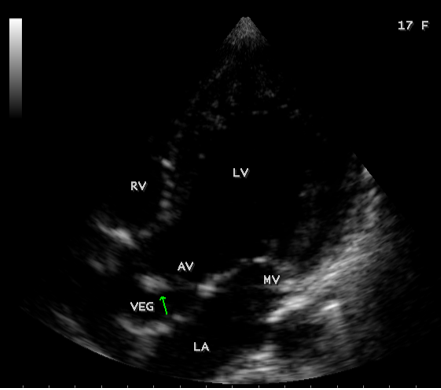

A 17-year-old female was brought to the emergency room with a history of sudden onset of breathlessness. Her pulse rate was 87 bpm and blood pressure 110/60 mmHg. She had a history of rheumatic fever during childhood, an episode of febrile illness for 10 days and taken antibiotic treatment recently. Blood chemistry revealed normal and blood cultures were negative. ECG revealed normal as shown in Figure 1 and X-ray chest revealed dilated LV (left ventricle) as in Figure 2. Physical examination revealed grade 3/6 early diastolic murmur over left mid sternal border, basal crackles over lung fields and no peripheral signs of wide pulse pressure. Transthoracic echocardiography revealed vegetations on anterior and posterior leaflets of aortic valve as in Figure 3 and Figure 4, with a “kissing-type “as in Figures 5, 6 and 8. The aortic valve was bicuspid with an attached vegetation as in Figure 9 and it was severely regurgitant as in Figure 10 and Figure 11. The left ventricle is dilated as in Figure 12 with moderate LV dysfunction as in Figure 13. The thoracic aorta was prominent as in Figure 14 with a ‘holodiastolic flow reversal’ as in Figure 15. The patient was treated with digoxin (0.25 mg, half daily), diuretics (Injection. Furosemide 20 mg IV twice daily), ACE inhibitors (tablet. Enalapril 2.5 mg twice daily) along with 2 weeks course of intravenous (IV) cefotaxime (1g) and amickacin (500mg) twice daily and advised aortic valve replacement at the earliest with lifelong penicillin prophylaxis and continuation of antibiotics for 6 weeks since the vegetations remain stable after 2 weeks of treatment, but without any embolic episodes.

Figure 7: Apical view showing the vegetation on the aortic valve (arrow) in a 17-year old female.

masses with atypical location. Transthoracic echocardiography detects 70% of vegetations > 6 mm and 25% of vegetation < 5>Figures 3 to 9. When endocarditis involves the aortic leaflets, the resultant acute, severe regurgitation as shown in Figures 10, 11 and 15, may often causes dilated left ventricle as in Figure 12 and a prominent aorta as in Figure 14. Secondary infection of mitral valve is a possible finding in primary aortic valve endocarditis. Large aortic valve vegetations (> 6 mm) prolapse into the left ventricular outflow tract and “kiss” the ventricular surface of the anterior mitral leaflet with the development of a vegetation [27],[28],[29]. The left ventricular outflow tract endocarditis may represent the initial site of infection with a possibility to spread by contiguity to both left-sided valves, the mitral and aortic [30], causes the “mitral-kissing vegetation” with a higher prevalence of embolic events [31].